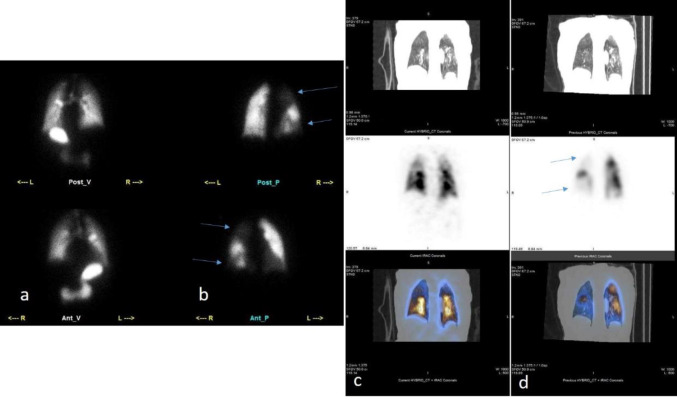

Methods: This was a cross-sectional study of patients with PCR-confirmed COVID-19 and suspected PE at a tertiary care hospital in 2020. They underwent ventilation/perfusion (V/Q) scintigraphy using single-photon emission computed tomography/computed tomography (SPECT/CT) and CT scans with or without contrast. Two blinded nuclear medicine physicians interpreted the images for PE and COVID-19. Clinical and laboratory data were extracted and analyzed.

Results: 96 patients with suspected PE and COVID-19 infection. The study excluded eight patients who could not undergo ventilation scans and confirmed PE in five patients with multiple mismatched V/Q defects on SPECT/CT. The study ruled out PE in 83 patients who had either regular perfusion scans, perfusion defects with COVID-19 features, or matched V/Q defects. The study found that the prevalence of PE was 5.68%, and the necessity of ventilation scans was 28.40% in this population.